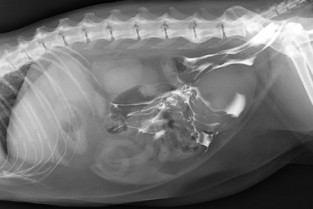

• d'utiliser l’imagerie pour explorer les épanchements thoraciques, les fistules cutanées, les abcès intra abdominaux ;

• de diagnostiquer par l’imagerie une torsion (autre que SDTE) ;

Lors d’uroabdomen, comment trouver la fuite ?

L'imagerie (radiographie / échographie) dans le diagnostic des épanchements pleuraux

L’épanchement péricardique : chien versus chat

Les abcès intra-abdominaux (prostatiques, hépatiques, spléniques..

Les shunts porto systémiques : de la suspicion au diagnostic

Cas cliniques imagerie thoracique (épanchement) - Groupe 2A

Cas cliniques imagerie abdominale (épanchement) - Groupe 2B

Cas cliniques imagerie abdominale (épanchement) - Groupe 1A